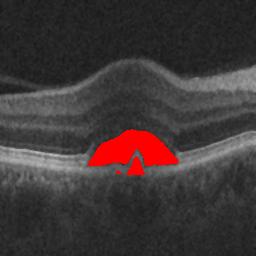

The qualitative results of the proposed system is shown in the Fig. 3. The detection task is evaluated using Area Under the Curve(AUC) metric and the segmentation task is evaluated using Dice Coefficient(DC) metric and the results are presented in Table1

|

|

| (d) De-noised OCT slice | (e)Predicted fluid region | (f)Manual fluid segmentation |

|

|

|

| (g) De-noised OCT slice | (h)Predicted fluid region | (i)Manual fluid segmentation |